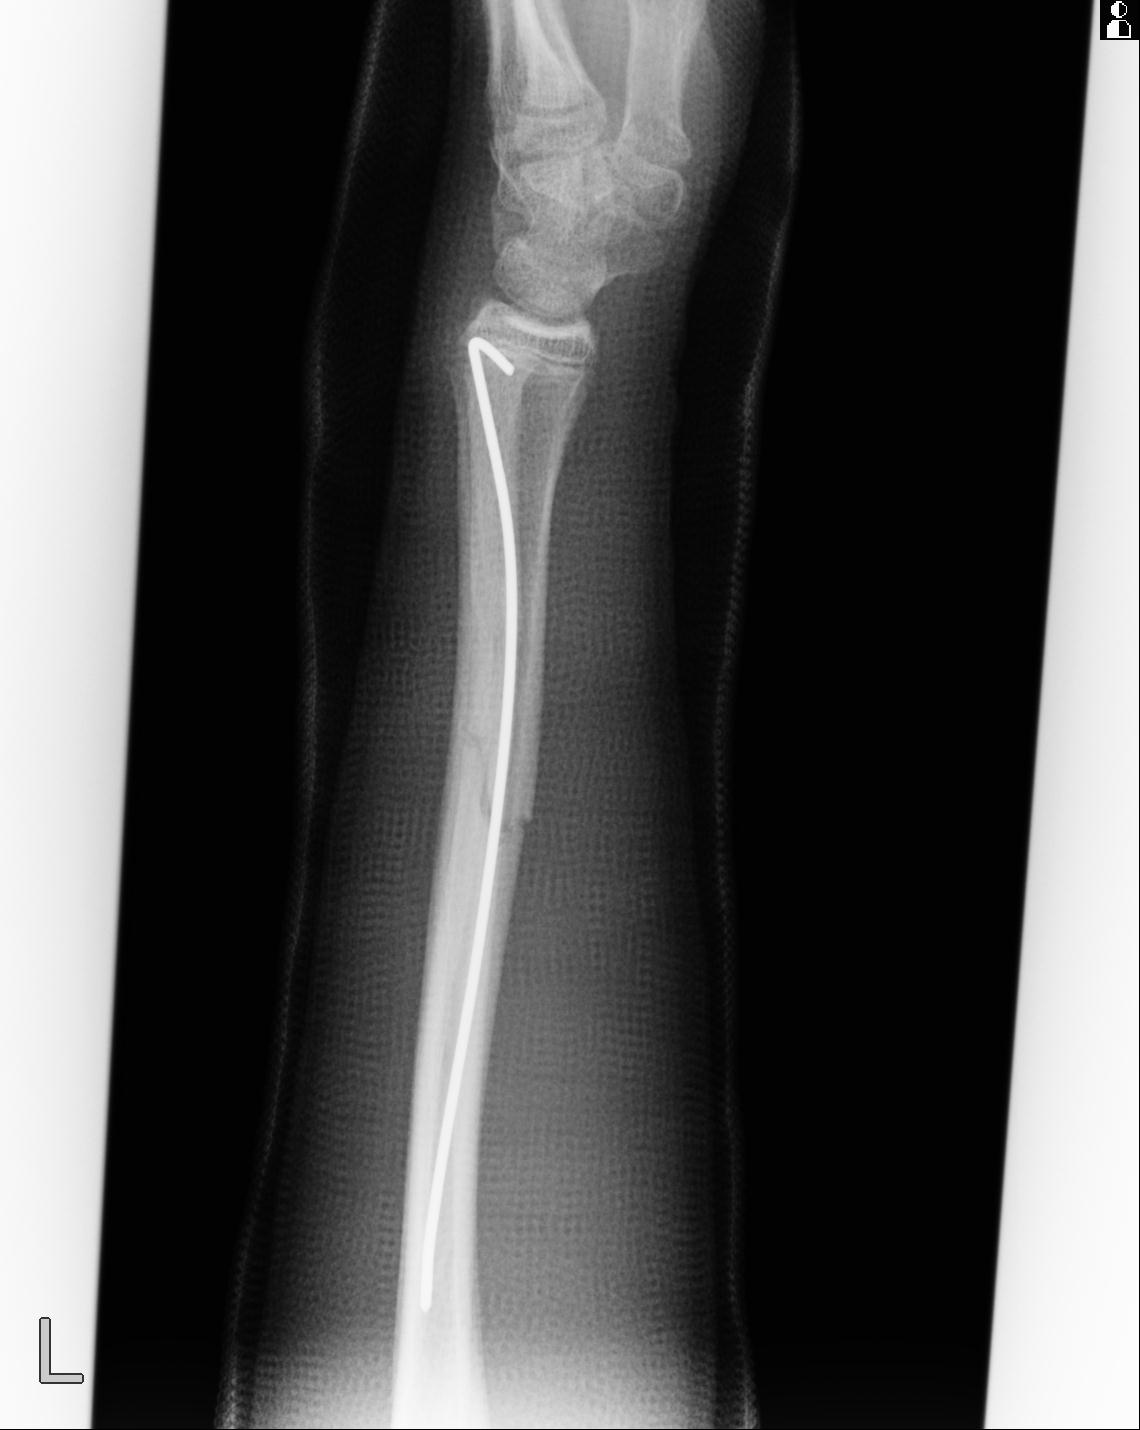

102803 1/12(キウスなし) 1/27 左下腿 4R 30歳女性 左脛骨軸内釘